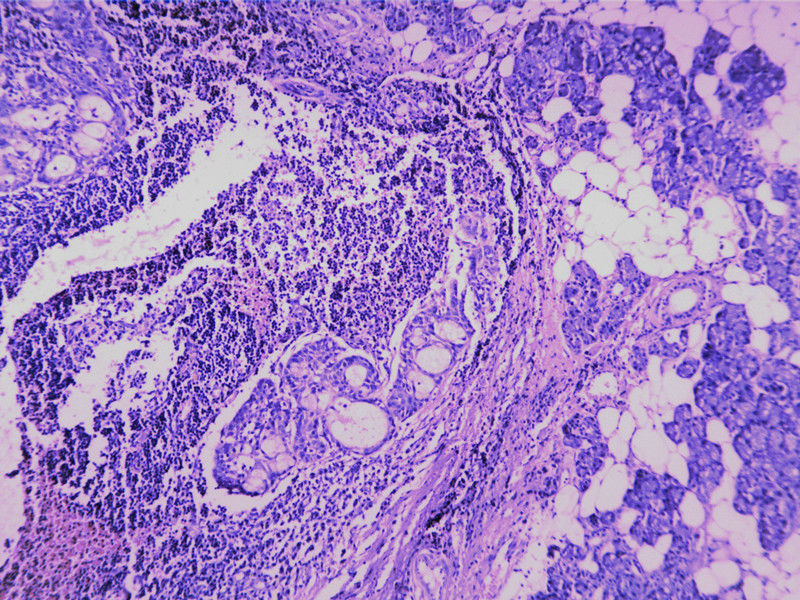

需要鉴别的肿瘤:

(1)皮脂腺淋巴腺瘤

(2)伴有淋巴组织间质的皮脂腺癌(皮脂腺淋巴腺癌)

(3)良性淋巴上皮病

(4)粘膜相关淋巴组织淋巴瘤(MALT淋巴瘤)

(5)转移性粘液表皮样癌